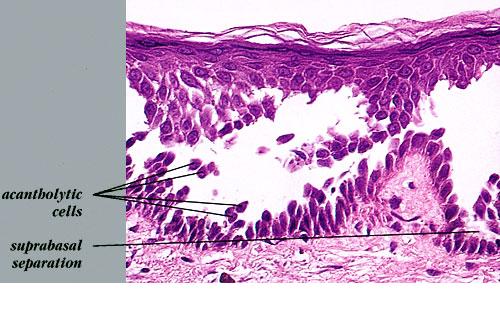

The earliest recognized change may be either eosinophilic spongiosis rarely or, more commonly, “spongiosis” in the lower epidermis . This spongiosis may actually represent the earliest manifestation of acantholysis rather than true spongiosis as defined earlier. Acantholysis leads first to the formation of clefts and then to blisters in a predominantly suprabasallocation . The intraepithelial acantholysis may extend into adnexal structures or occasionally be higher in the stratum spinosum. The basal keratinocytes, although separated from one another through the loss of attachment, remain firmly attached to the dermis like a “row of tombstones.” Within the blister cavity, the acantholytic keratinocytes, singularly or in clusters, have rounded condensed cytoplasm about an enlarged nucleus with peripherally palisaded chromatin and enlarged nucleoli. In some patients, there are varying quantities of antidesmoglein 1 and antidesmoglein 3 antibodies, leading to variable planes of acantholysis. There is little inflammation in the early phase of blister formation. If present, it is usually a sparse, lymphocytic perivascular infiltrate accompanied by dermal edema. However, if eosinophilic spongiosis is apparent, numerous eosinophils may infiltrate the dermis. The phenomenon of eosinophilic spongiosis occurs occasionally in other blistering diseases, particularly in their early phases, including acute contact dermatitis, pemphigus foliaceus, bullous pemphigoid, herpes gestation is, drug eruptions, spongiotic arthropod bite reactions, and transient acantholytic dermatosis. Several important changes ensue as the lesions age. First, a mixed inflammatory cell reaction consisting of neutrophils, lymphocytes, macrophages, and eosinophils may develop. Because of the instability of the blister roof, erosion and ulceration may occur. Older blisters may also have several layers of keratinocytes at the blister base because of keratinocyte migration and proliferation. Last, there may be considerable downward growth of epidermal strands, giving rise to so-called villi (Fig. 9-9D). The evaluation of patients with only oral lesions is difficult, because intact blisters are rarely encountered due to the trauma of mastication, and biopsies may show only erosion and ulceration. Indeed, it is best to sample the edge of a denuded area with intact mucosa in an attempt to demonstrate the typical pathologic changes. Clinicians frequently cannot distinguish between an ulcer and the intact mucosa, as both are often white and shaggy. In patients with only oral lesions, biopsies of intact oral mucosa for DIF testing are more sensitive than biopsies of lesions for routine light microscopic evaluation. Therefore, biopsy from the normal maxillary and upper buccal mucosa is necessary when there is extensive ulceration. Cytologic examination using a Tzanck preparation is useful for the rapid demonstration of acantholytic epidermal keratinocytes in the blisters of pemphigus vulgaris. For this

Differential DiagnosisIn early blisters that are free of secondary changes, such as the degeneration or regeneration of epidermal cells, the histopathology of pemphigus vulgaris is characteristic. Important differential diagnoses include Hailey-Hailey disease and transient acantholytic dermatosis. Hailey-Hailey disease has full­thickness (“dilapidated brick wall”) acantholysis, epidermal hyperplasia, and an impetiginized scale crust. The acantholysis does not extend down follicles as it does in pemphigus. Transient acantholytic dermatosis may exhibit small foci of intraepidermal acantholysis, but these are only a few rete wide in contrast to the uniform widespread acantholysis observed in biopsies of pemphigus vulgaris. Disorders such as Darier’s disease that are characterized by acantholytic dyskeratosis are readily separated from pemphigus vulgaris by the presence of abnormal granular keratinocytes and parakeratotic cells, so-called corps ronds and corps grains. Although light microscopic examination of pemphigus lesions is important, positive DIF is the gold standard in diagnosis at this time and must be pursued in all cases in which pemphigus vulgaris is considered.